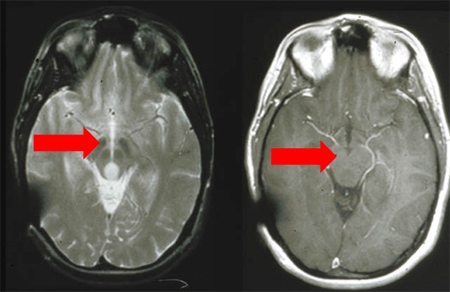

[Figure caption and citation for the preceding image starts]: MRI: T2 and T1 post-contrast, demonstrating a tectal glioma (grade II).From the personal collection of Karine Michaud, University of California, San Francisco; used with permission [Citation ends].